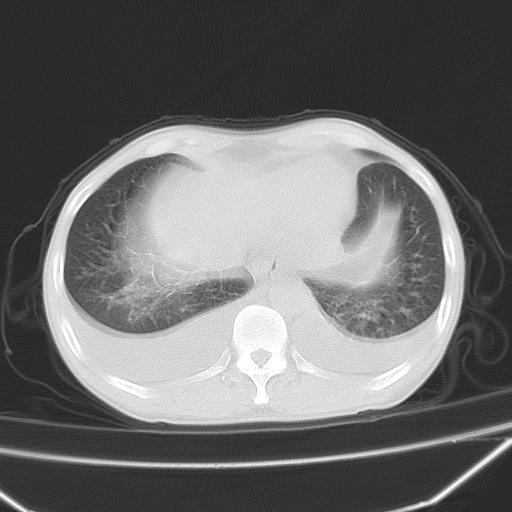

男、42岁、咯血3天。既往有甲亢、贫血、血尿蛋白尿史多年。血象:wbc:6.   中性粒:70.6%。

双肺野对称性磨玻璃影,分布于内中带,双侧胸水,患者有咯血。

双肺野广泛对称性磨玻璃影、实变影,以肺门为中心,主要分布于内中带,符合典型肺泡性肺水肿;伴双侧胸腔少量游离积液。结合患者既往病史且咯血就诊,支持多因素(尿毒症等)所致之肺水肿、肺出血、胸水;影像表现暂不考虑心源性水肿,且症状也不太符。需密切随诊结合临床治疗等进一步明确。

双肺堆成磨玻璃影,双测胸腔积液。考虑:肺水肿、间质性肺炎、真菌感染、ards、hiv感染、肺出血。